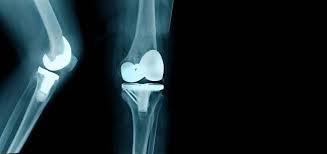

Joint replacement surgery has revolutionized the field of orthopedics, offering new hope to millions of individuals suffering from chronic joint pain and limited mobility. Whether it’s due to age-related wear and tear, injury, or degenerative conditions like osteoarthritis, joint replacement surgery has become a life-changing option for many. In this article, we will explore the advancements in joint replacement surgery and how it has significantly improved the quality of life for countless patients.

One of the key advancements in joint replacement surgery is the development of improved materials for prosthetic joints. In the past, joint replacements were made primarily of metal and plastic components. Today, advancements in biomaterials have led to the creation of highly durable and biocompatible materials like ceramic and metal alloys. These materials mimic the natural joint’s structure and function, providing a more natural range of motion.

The integration of computer-assisted technology has greatly improved the precision and accuracy of joint replacement surgeries. Surgeons can now use computer navigation systems to ensure the perfect alignment of the prosthetic joint, leading to better long-term outcomes and reduced complications.